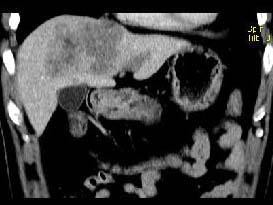

根据所提供的图像,最可能的诊断是()

A.肝血管瘤

B.局灶性结节增生

C.肝癌

D.结节性肝硬化

E.肝转移癌